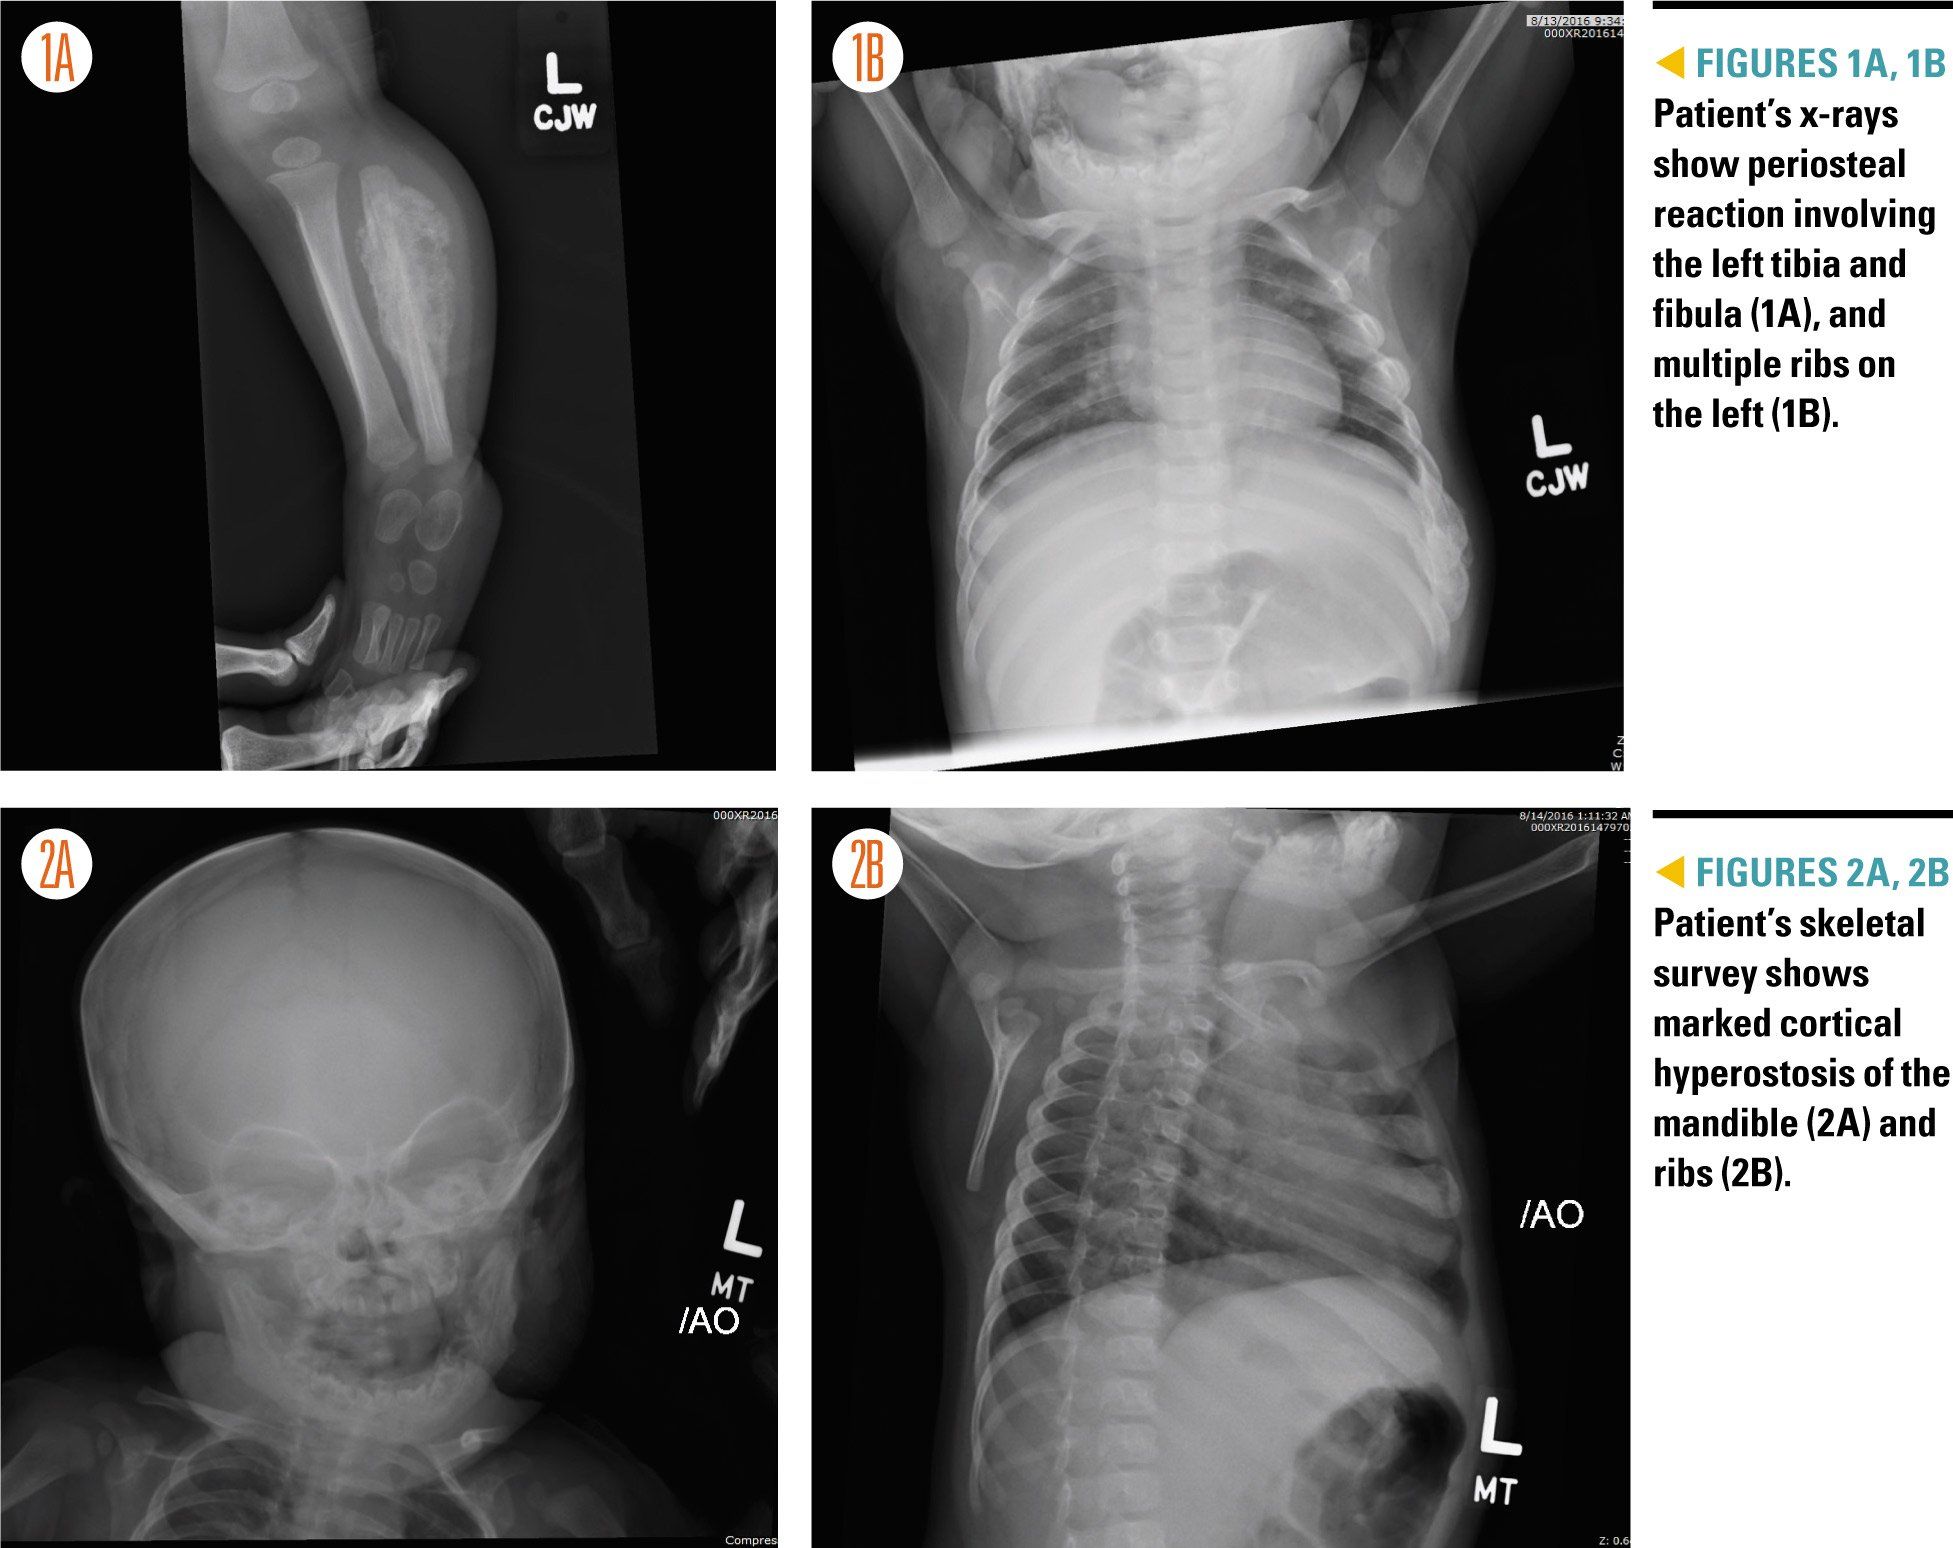

Figures 1A,1B, 2A, and 2B

Laboratory studies revealed an elevated white blood cell count (20.15 K/uL) as well as an elevated platelet count (722 K/uL) and elevated inflammatory markers (C-reactive protein, 5.0 mg/dL; erythrocyte sedimentation rate, 44 mm/h). A comprehensive chemistry panel, lactate dehydrogenase, and uric acid were unremarkable. Additionally, x-rays of the patient’s left lower extremity and chest were obtained, which preliminarily showed marked periosteal reaction involving the left tibia and fibula and multiple ribs on the left (Figures 1A and 1B).

The Orthopedic Surgery and Oncology services were consulted due to a strong concern for malignancy. A skeletal survey was obtained (Figures 2A and 2B), and the patient was admitted to the Oncology Service for further management, with the tentative plan by Oncology to obtain an MRI of the left leg and a computed tomography (CT) scan of the chest the following morning.

Upon further review of the patient’s x-rays and skeletal survey, multiple specialists-including pediatric radiologists-agreed that the imaging showed marked cortical hyperostosis of the mandible, ribs, and left tibia and fibula-diagnostic of Caffey disease.